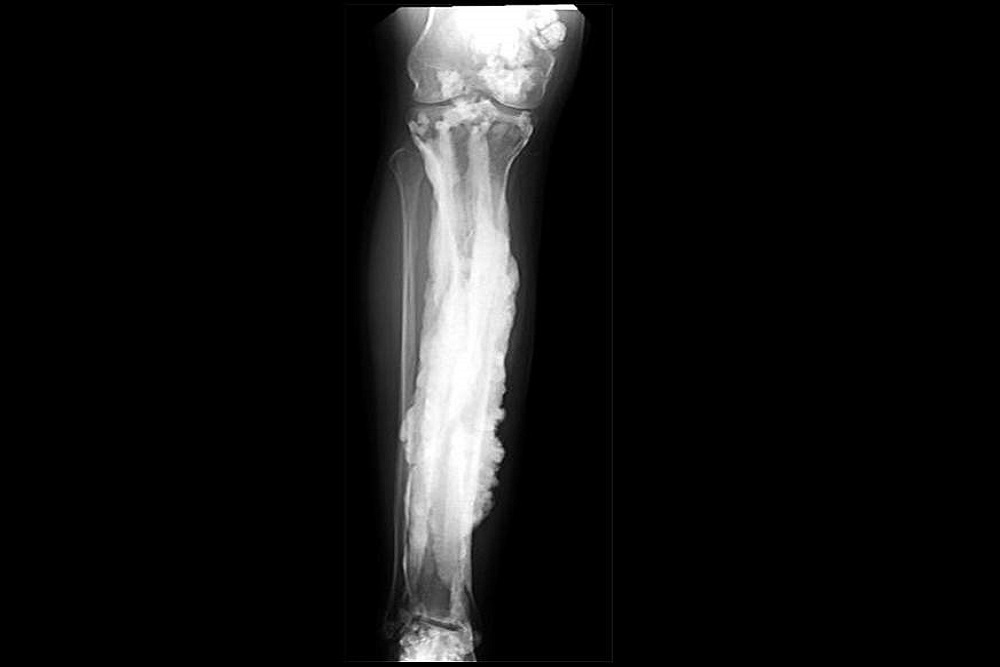

The rare disorder, known as melorheostosis, causes excess bone formation that resembles dripping candle wax on x-rays. The results, appearing in Nature Communications, offer potential treatment targets for this rare disease, provide important clues about bone development, and may lead to insights about fracture healing and osteoporosis.

Though there are only about 400 known cases of this disorder worldwide, 15 unrelated adults with the condition from around the globe volunteered to come to the NIH Clinical Center to undergo biopsies of both affected and unaffected bones. The condition causes pain and bone deformity, which can limit the function of bones.